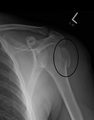

![]() Comminuted midshaft humerus fracture with callus formation | |

Proximal humerus fracture